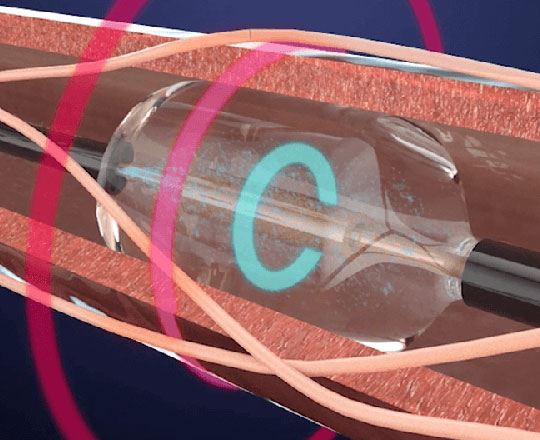

True Flow (Bard, EEUU) es un balón de valvuloplastia que permite el flujo a su través mientras está inflado. Su recubrimiento exterior está compuesto por un tejido de fibras que evita el deslizamiento del balón al abrirse sobre los velos valvulares, por lo que no se necesita estimular el corazón con marcapasos. Este tejido esta formado por poliuretano de alto peso molecular, poliéster y fibras de aramida (componente estructural del Kevlar) que posee una baja distensibilidad y alta resistencia a la rotura. El interior del balón tiene 8 globos de pequeño diámetro en el perímetro del balón principal, y deja un espacio entre ellos por donde fluye la sangre. El dispositivo mide 3,5 cm de largo y está disponible en seis tamaños, con diámetros que van de los 18 a los 26 mm. Los más pequeños son compatibles con un introductor de 11 French y el más grande con introductor de 16 French.

Este tipo de balón permite realizar la valvuloplastia durante 60 s o incluso más sin estimulación rápida, con una disminución de 1/3 de la presión media aórtica durante el inflado, lo que garantiza reducciones del 50% en el gradiente aórtico. Algo de gran utilidad cuando los enfermos tienen una disfunción grave.